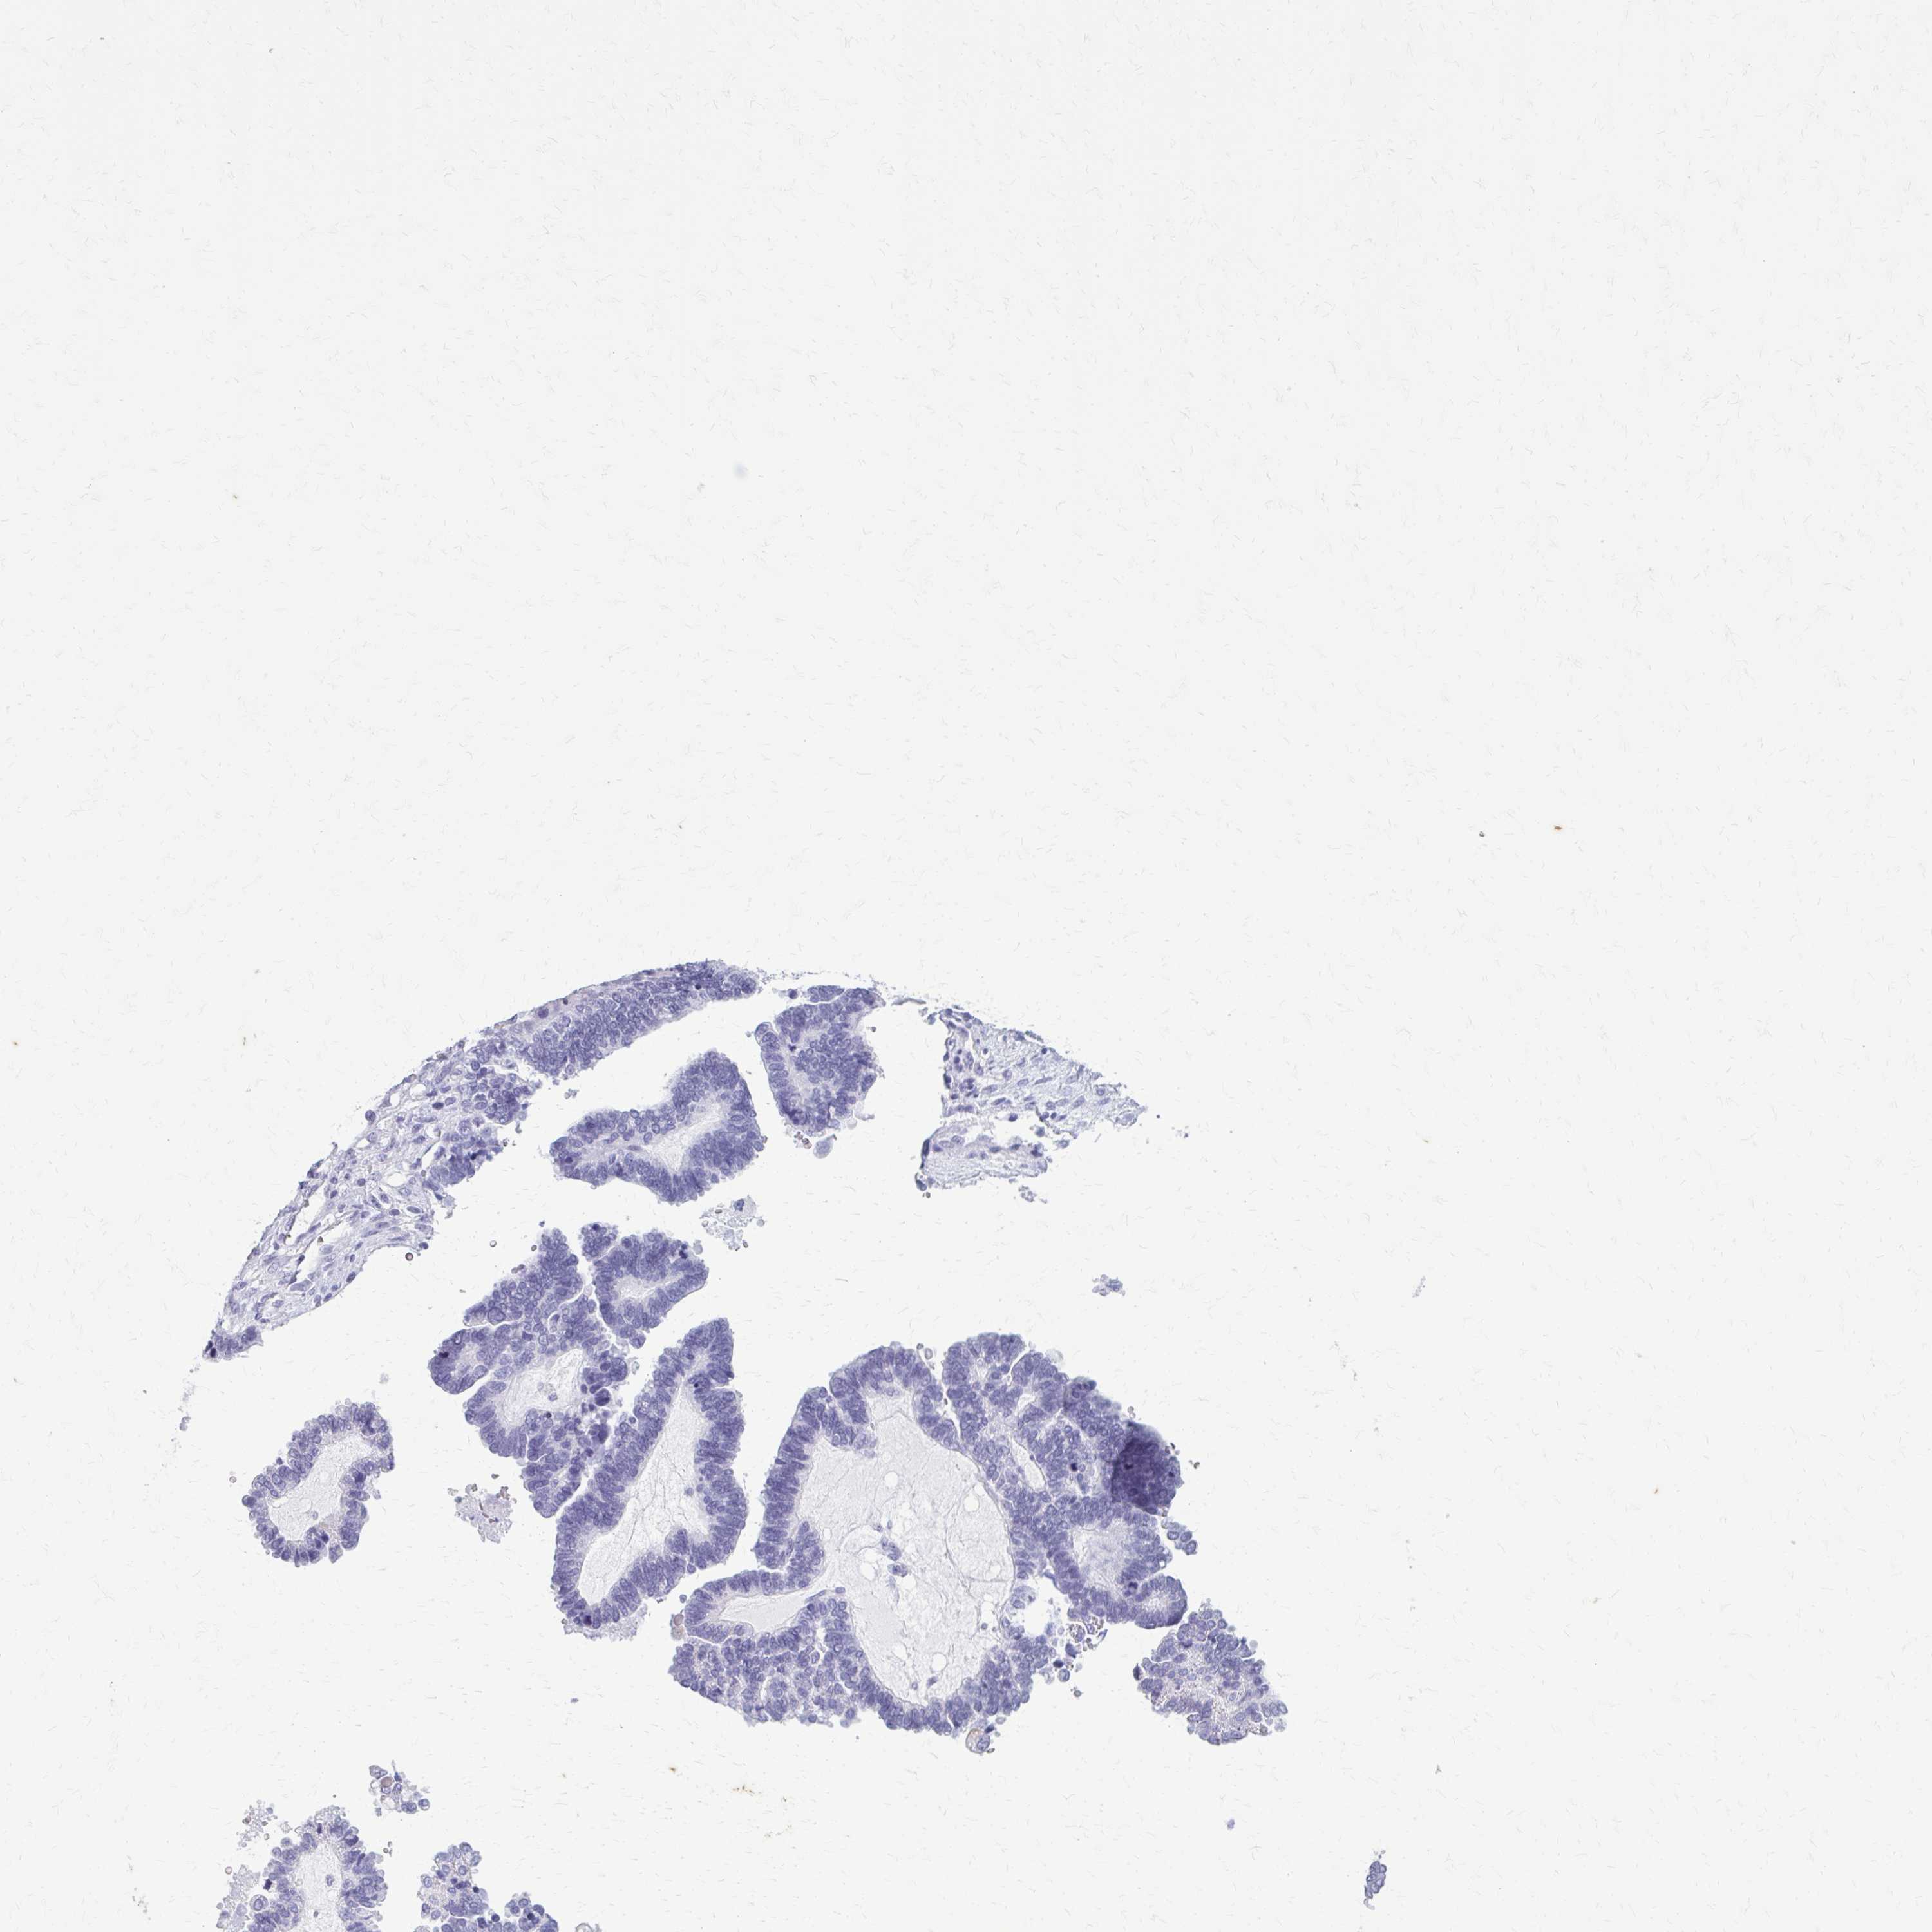

OVARIAN CANCER - Protein expressioni

A mouse-over function shows sample information and annotation data. Click on an image to view it in a full screen mode. Samples can be filtered based on level of antibody staining by selecting one or several of the following categories: high, medium, low and not detected. The assay and annotation is described here.

Note that samples used for immunohistochemistry by the Human Protein Atlas do not correspond to samples in the TCGA dataset.

Antibody stainingi

Antibody staining in the annotated cell types in the current human tissue is reported as not detected, low, medium, or high, based on conventional immunohistochemistry profiling in selected tissues. This score is based on the combination of the staining intensity and fraction of stained cells.

Each image is clickable and will lead to virtual microscopy that enables deeper exploration of all samples and also displays staining intensity scores, fraction scores and subcellular localization as well as patient and tissue information for each sample.

Antibody HPA059479

Antibody CAB000027

Antibody CAB000129

Antibody CAB080101

Cystadenocarcinoma, mucinous, NOS